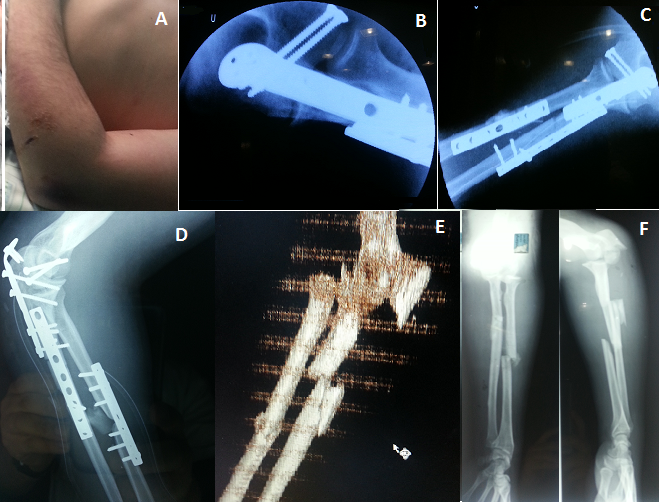

Coude flottant associant une fracture de Monteggia Bado 4 à une fracture de la palette humérale

Le coude flottant représente une association lésionnelle peu fréquente en traumatologie et qui pose un problème pronostique et fonctionnel majeur. D'où l'importance d'un diagnostic précis avec une prise en charge rapide et adéquate des blessés. Une ostéosynthèse stable de l'ensemble des lésions doit être recommandée permettant une rééducation précoce. La hiérarchisation des gestes s'impose en fonction du type anatomopathologique des lésions. Il s'agit d'images cliniques et radiologique per, pré et post opératoire d'un coude flottant chez un patient de 40 ans suite à un accident de voiture associant une fracture de la palette humérale métaphyso-épiphysaire à une fracture de monteggia type 4 selon la classification de Bado (fractures des deux os de l'avant bras avec luxation de la tête radiale). Traitement chirurgical : voie d'abord postérieure pour le 1er temps : réduction et vissage de la palette humérale profitant de la fracture de l'olécrane pour une très bonne exposition de la palette humérale. 2ème temps : réduction et ostéosynthèse de la fracture bifocale comminutive du cubitus par 2 plaques vissées dont une en crochet pour l'olécrane, réduction spontanée de la tête radiale. 3ème temps : réduction et ostéosynthèse de la fracture du radius par une plaque vissée, voie d'abord antéro-externe.